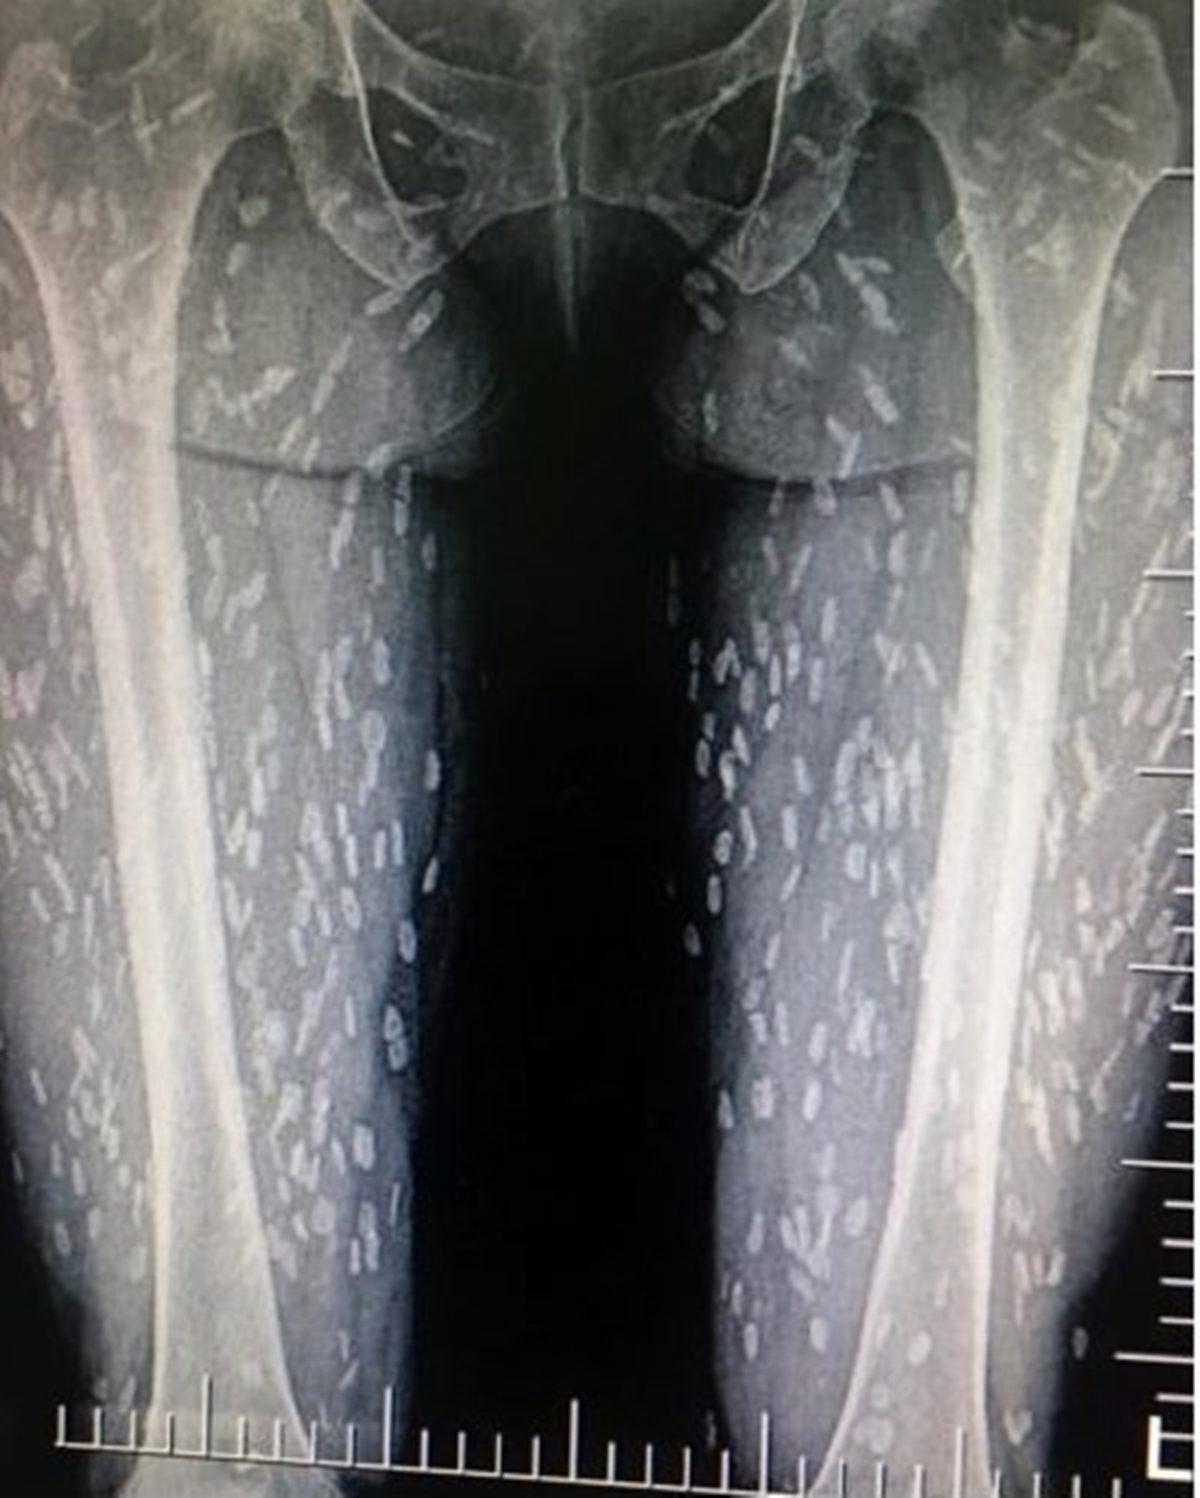

- Yemeklerini pişirmeden yiyen Taylandlı bir kadın, vücudunda bir gariplik hissedip doktora gidince içinde yüzlerce parazit olduğu ortaya çıkmış.